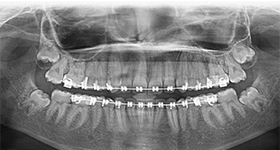

Orthodontics is the branch of dentistry which deals with the alignment of irregular or crooked teeth. While most people are treated with orthodontic braces in their teens, we at Amrapali Dental believe the best time to be examined by a dentist is when a child is six years old. Frequently, we are able to avoid major orthodontic work in later years by using space maintaining devices to avoid overcrowding of teeth.

Thanks to recent advances, the metallic orthodontic brackets which we’re so used to seeing can now be replaced by a far less conspicuous ceramic, see through bracket, so braces don’t have to make you or your children self conscious anymore. We also specialize in lingual orthodontics, where we place the orthodontic wire on the back surface of your teeth, completely out of sight. In certain cases, you might also be a candidate for the revolutionary new Invisalign clear orthodontic trays.

Remember, there is no age limit to start orthodontic treatment. Orthodontics for adults is very popular worldwide, and the orthodontists at Amrapali Dental Clinic will work to align your teeth beautifully to give you that smile which makes you look as young as you feel !